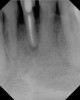

Figure 7  Clinical case of internal root resorption that was treated by orthograde root canal therapy.

Figure 7

Figure 8  Clinical case of internal root resorption that was treated by orthograde root canal therapy.

Figure 8